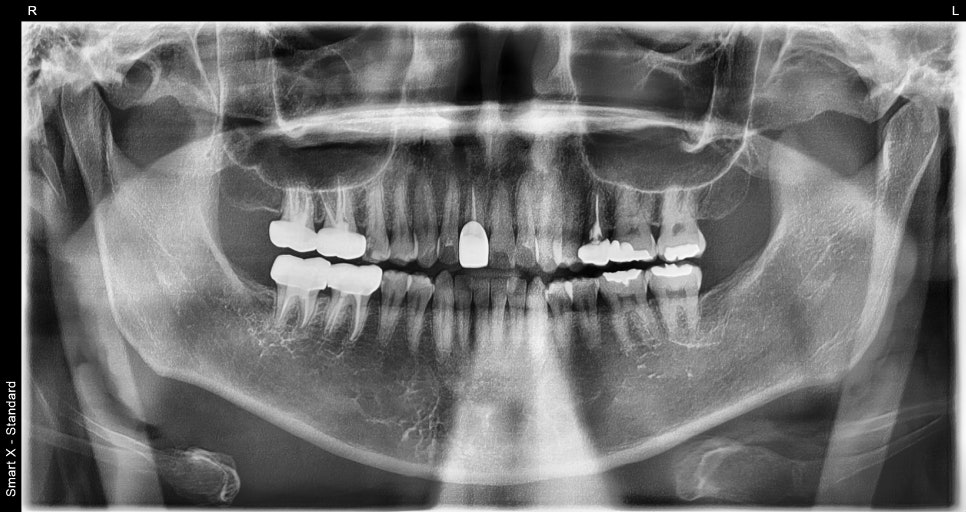

치과에서는 제일 먼저

치아 뿌리가 괜찮은지,

잇몸뼈가 건강한지

이 두 가지를 확인해요.

엑스레이를 확인해보니 충치가 너무 심해 치아가

깨진 상태로 오셨어요.